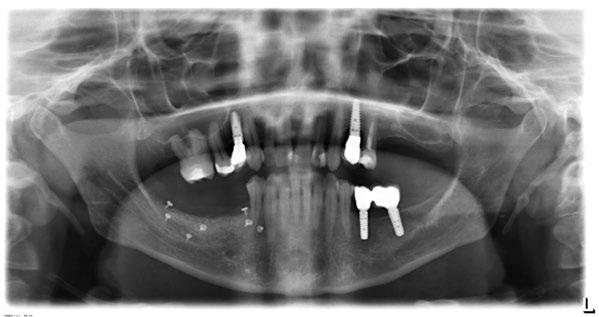

Figura 14. Imagen intraoral frontal postoperatoria al año de la reconstrucción.

Figura 15. Detalle de prótesis dentoalveolar cerámica en visión lateral.

Figura 16. Ortopantomografía postoperatoria.

Figura 17. Resultado final.